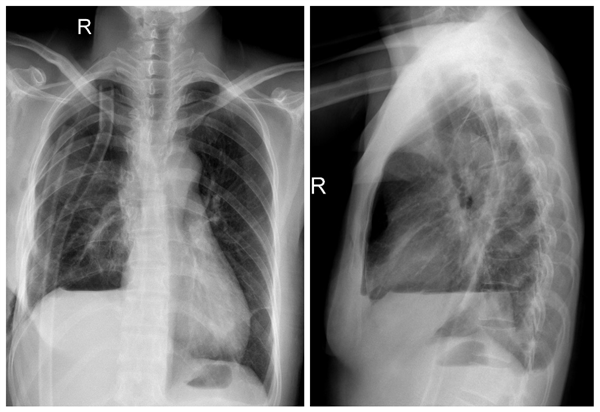

患者吕某某,女,43岁,因“间断咳嗽咳痰3年,胸痛伴活动后胸闷气短2月” 于2020年03月25日入住我院呼吸与危重症医学科。入院后行胸部增强CT提示右主支气管壁不均匀增厚,不除外纵隔内结节压迫/侵犯,纵隔淋巴结肿大。行支气管镜检查可见右主支气管开口肿物阻塞管腔,肿物呈结节状,凸向隆突,表面尚光滑,血供较丰富,内镜勉强通过,通过后见右肺中下叶开口,管腔通畅,活检病理结果为腺样囊性癌。考虑病变位置特殊且完全堵塞右住支气管并距离隆突较近,内科保守治疗效果差,经李少民主任会诊并与患者及家属沟通后转胸外科进一步治疗。转科后,在进一步完善术前检查的同时,李少民主任积极向院方申报重大手术申请,并邀请急诊ICU裴红红主任、麻醉科薛荣亮教授及心血管外科张伟主治医师来我科进行多学科会诊,经多方讨论后最终决定手术方案为在ECMO支持下行气管肿瘤切除、隆突重建气管成形术。经过充分的术前准备,4月17日上午,在麻醉科团队先进行全身麻醉后,急诊科团队立即进行VV-ECMO连接,确保患者呼吸功能的维持,随后胸外科李少民主任团队进行手术操作,术中充分游离并显露肺门结构,完整切除了肿瘤侵及的右肺上叶、部分主气管、隆突及部分左右主支气管,并成功完成主气管与左主气管吻合,左主支气管与右肺中间支气管的吻合重建隆突,手术过程顺利,历时3小时,术后患者生命体征平稳,顺利脱离ECMO、拔除气管插管后安全返回胸外科监护室,目前患者病情稳定,术后复查胸片肺复张良好。